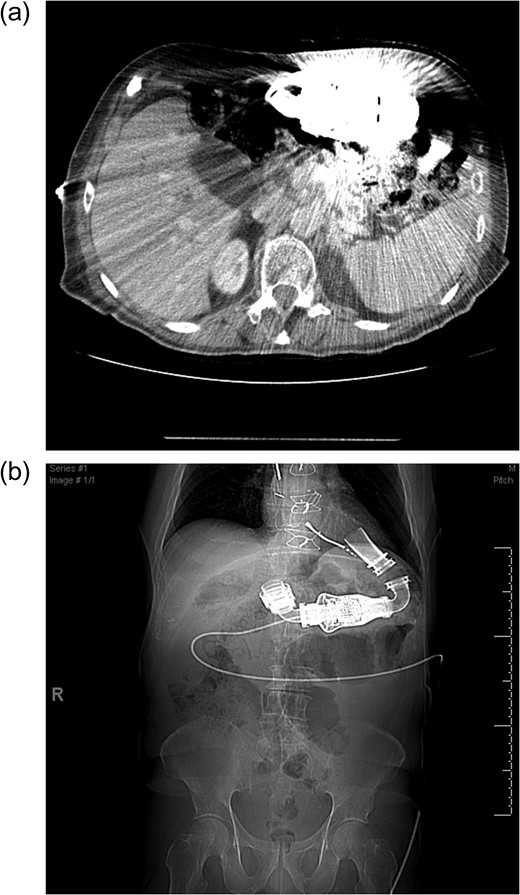

(a) Cross sectional imaging as a pre-operative study to define the pancreatic anatomy is limited by the LVAD artifact. (b) Computed tomography scout film shows the location of the LVAD and LVAD driveline in the chest and abdomen.

Due to LVAD streaking artifact on CT, pre-operative good quality imaging of the pancreas was only possible with endoscopic ultrasound.